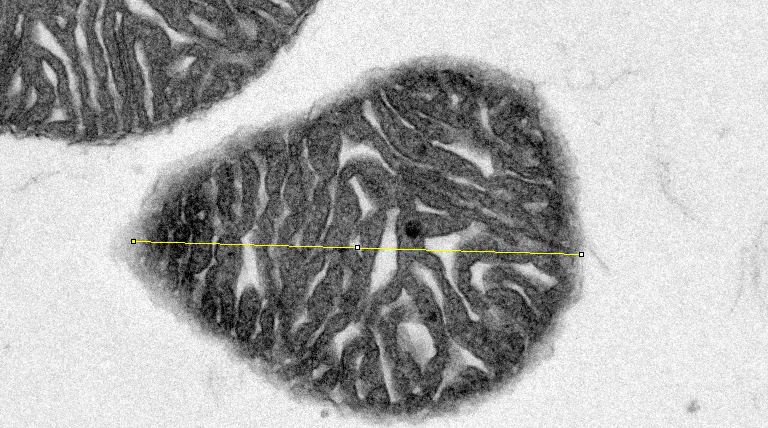

(3) 线粒体长宽比

按照上述方法打开ROI Manager设置框,选择主界面直线工具

对目标线粒体长轴画直线→点击Add,出现长轴项目编号(蓝色框

类似的,对目标线粒体短轴画直线→点击Add,出现短轴项目编号(绿色框)→点击Measure计算结果,说明选中线粒体长轴为1.335μm,短轴为1.036μm,长宽比计算后为1.289